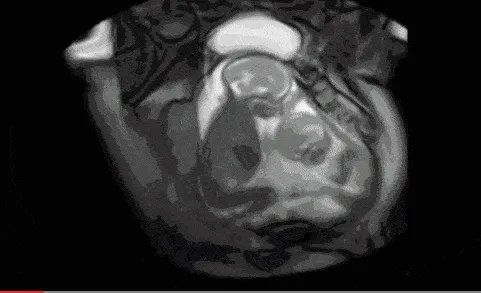

那天看到宁夏双胞胎在肚子里打架的视频,感觉特别可爱,这对双胞胎已经平安出生,

具体是这样的,一个怀有双胞胎的孕妇去做产检时,发现两个孩子在打架,你一拳我一拳,推推搡搡,嘴里好像念念有词,战斗了几个回合不停止,把在场的人引得哈哈大笑。

之前网上面曾经看到过这样的一组动图,是双胞胎妈妈的B超影像。只见两个宝宝在一起,其中一个宝宝很是活跃,对着另外一个宝宝,一会动一下手,一会动一下脚的。从外面看起来就像是两个宝宝在打架一样。